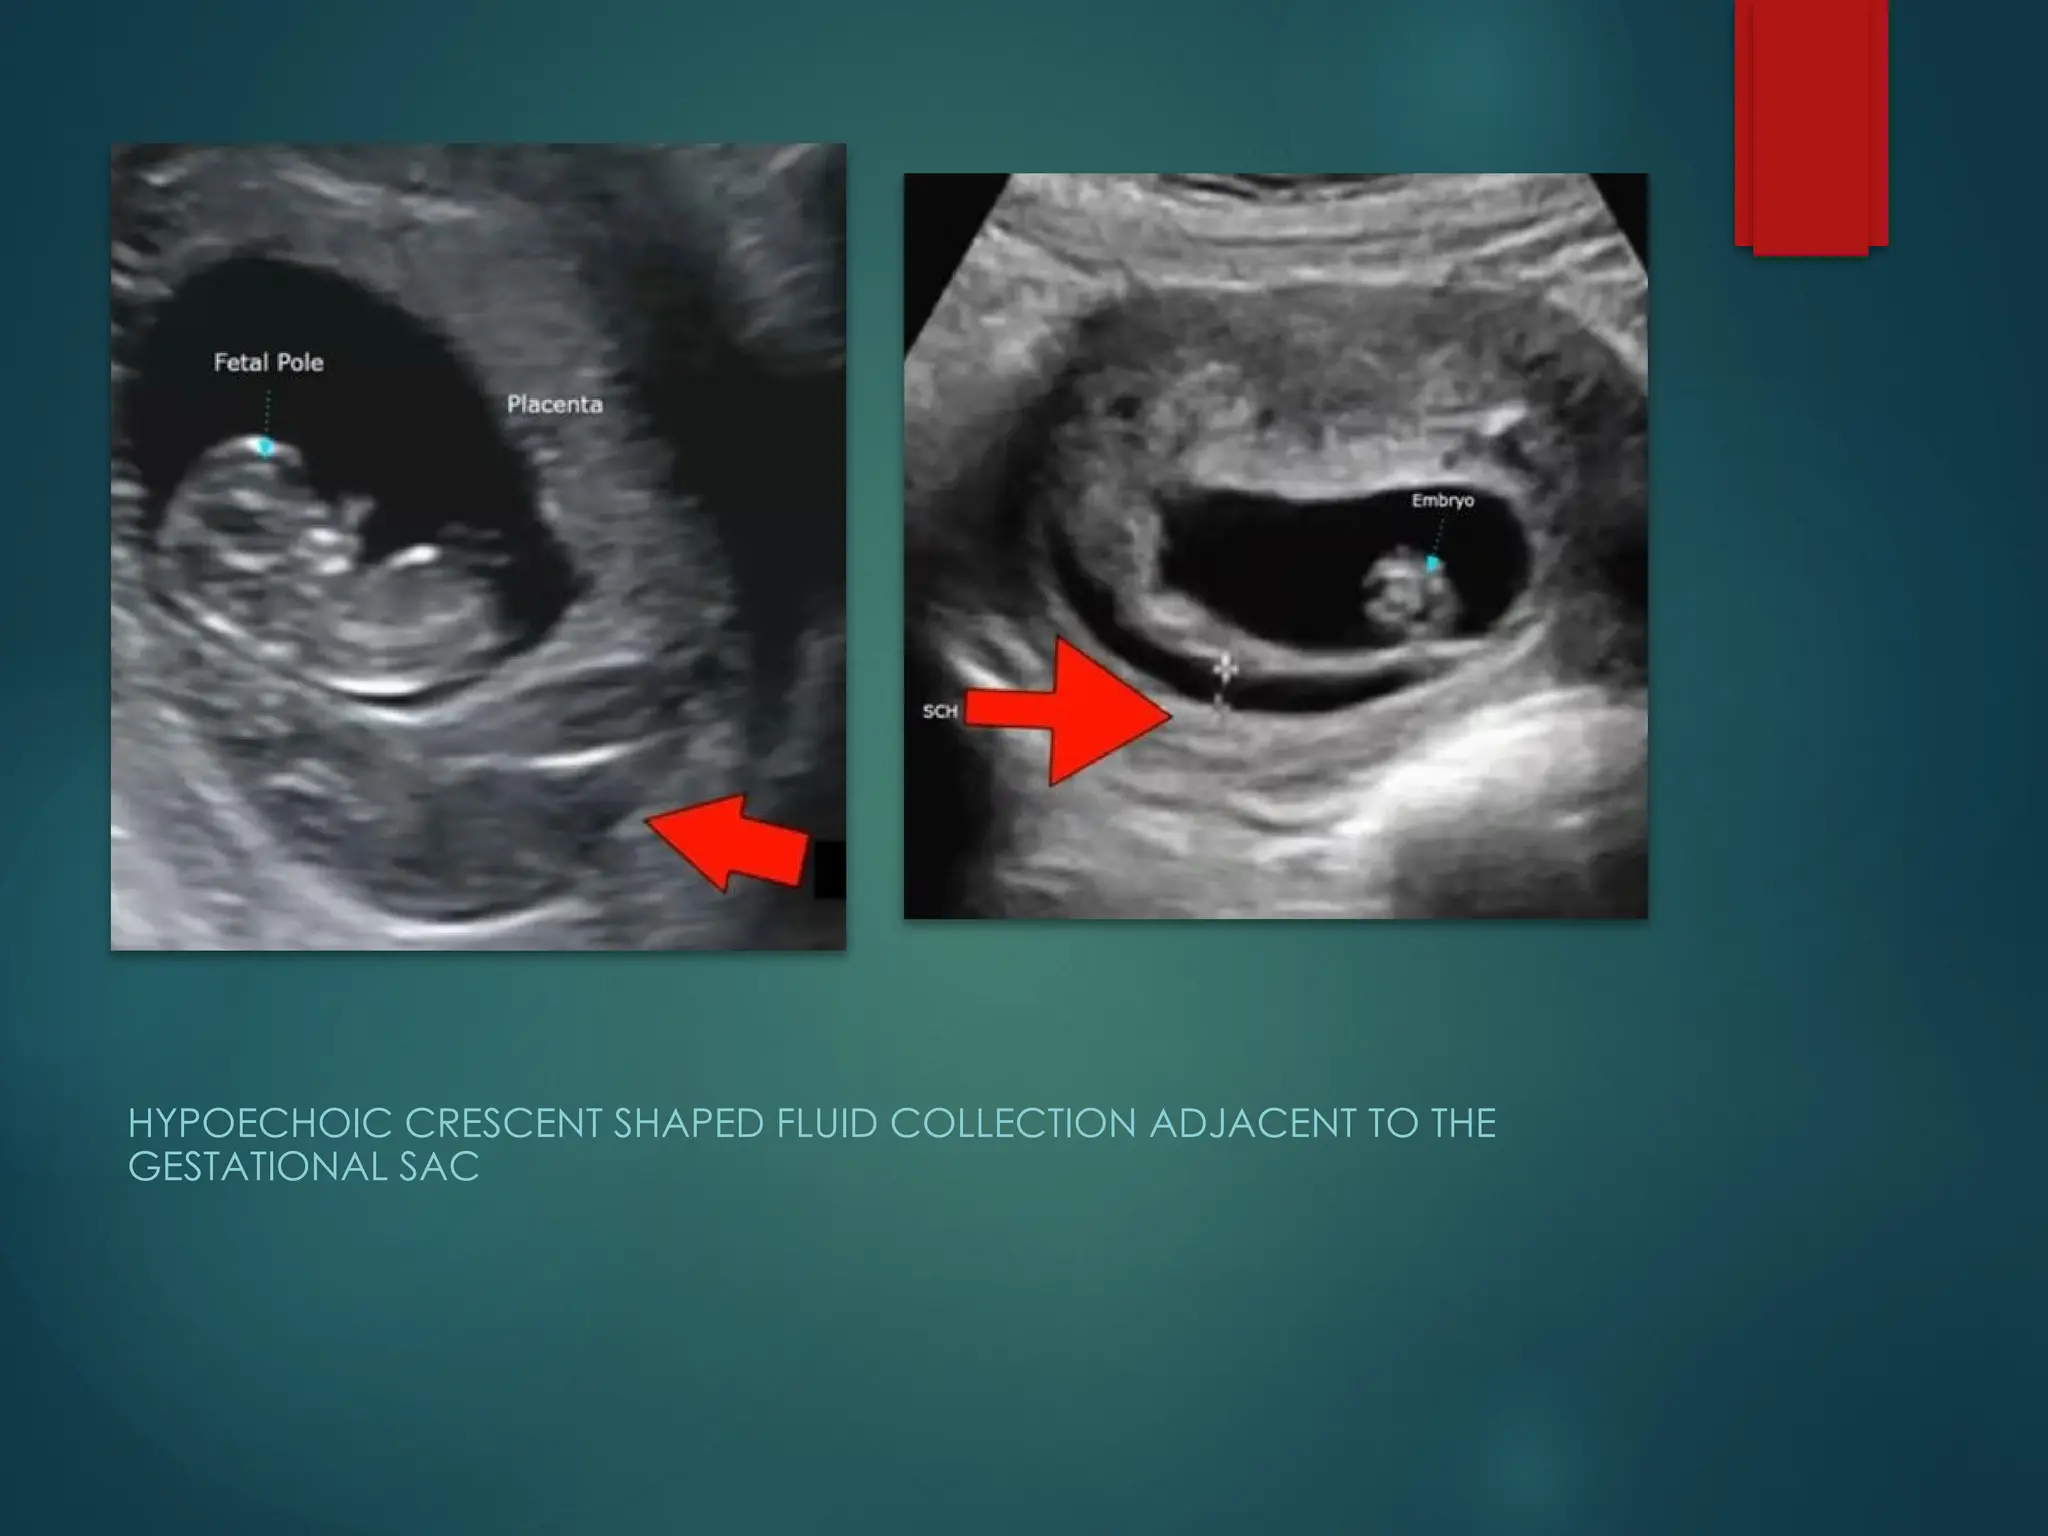

SUBCHORIONIC HAEMORRHAGE

SCH:

HYPOECHOIC AREA

BETWEEN THE

GESTATIONAL SAC AND

UTERINE WALL

HYPOECHOIC CRESCENT SHAPED FLUID COLLECTION ADJACENT TO THE

GESTATIONAL SAC

SCH >50%

of GS size

Acute SCH

appears

hyperechoic

and may

cause difficulty

to differentiate

from the

adjacent

chorion

Hypoechoic

fluid collection

adjacent to

gestational

sac

with lack of

blood flow on

colour doppler